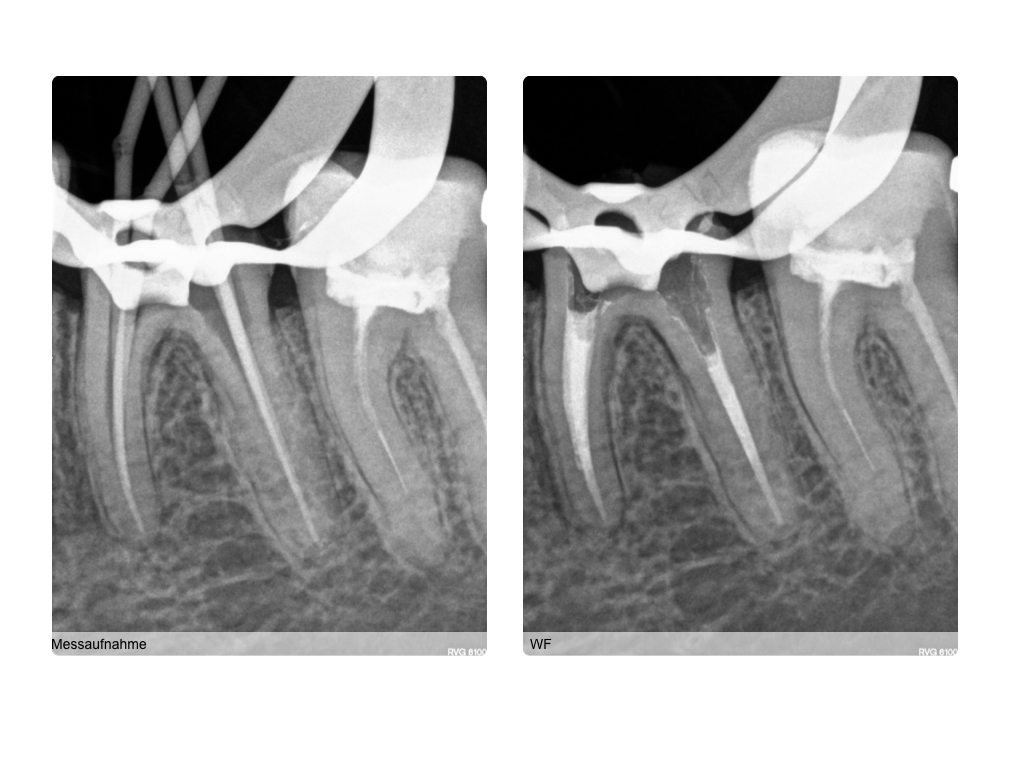

ws15102016-013

4 auf einen Streich